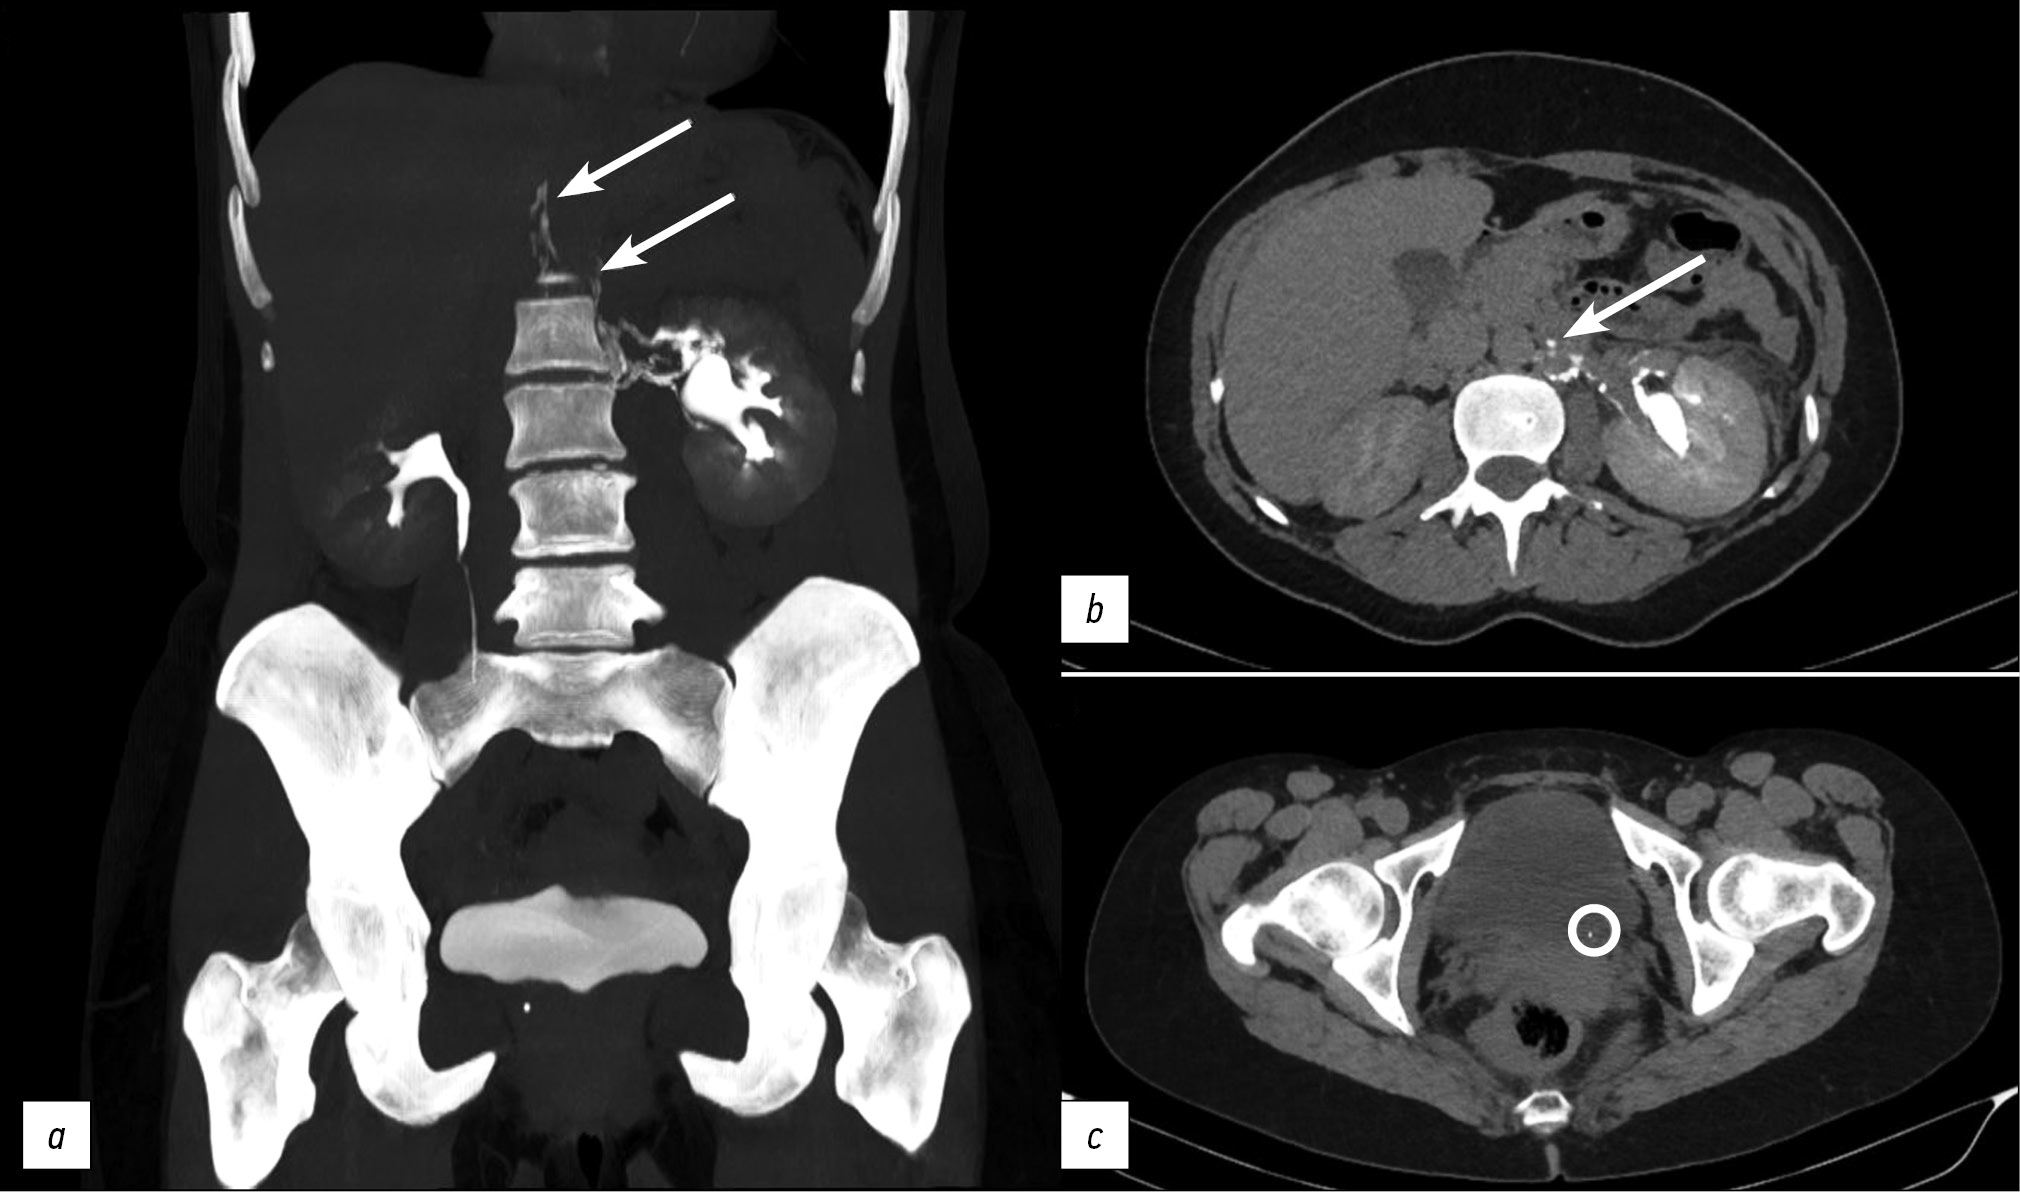

This article presents two clinical observations of uro-lymphatic fistulas diagnosed by computed tomography. In both cases, the patients were admitted with symptoms of renal colic. Uro-lymphatic fistulas are a rare condition caused by the formation of a connection between the urinary and lymphatic systems, which is caused by, as a rule, lymphatic vessel obstruction due to parasitic infestation. Other causes may be radiation therapy, retroperitoneal trauma, and tumor sprouting. In the era before antibiotics, infectious processes such as xanthogranulomatous pyelonephritis and renal tuberculosis were common. Cases of uro-lymphatic fistulas formed against urolithiasis background are presented below. In the clinical cases presented, urine directly entered the lymphatic vessels through a uro-lymphatic fistula detected on contrast-enhanced computed tomography. Uro-lymphatic fistulas caused by impaired urine outflow due to blocked urinary tract are rarely detected since abdominal ultrasound is the diagnostic method of choice in renal colic. In the vast majority of cases, uro-lymphatic fistulas are treated conservatively and do not require surgical intervention. As a rule, the formed fistulas cease to exist when its root cause is successfully treated.